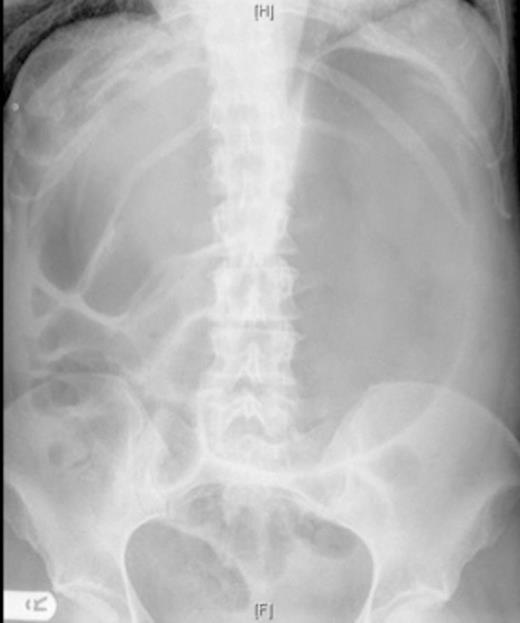

On examination, her abdomen was soft but distended, with tenderness in the epigastric region. The abdomen was hyperresonant on percussion. The patient had a chest x ray which demonstrated cardiomegaly and an abdominal x ray (figure 1).

AP abdominal radiograph; markedly distended stomach and distension of bowel loops in the right upper quadrant